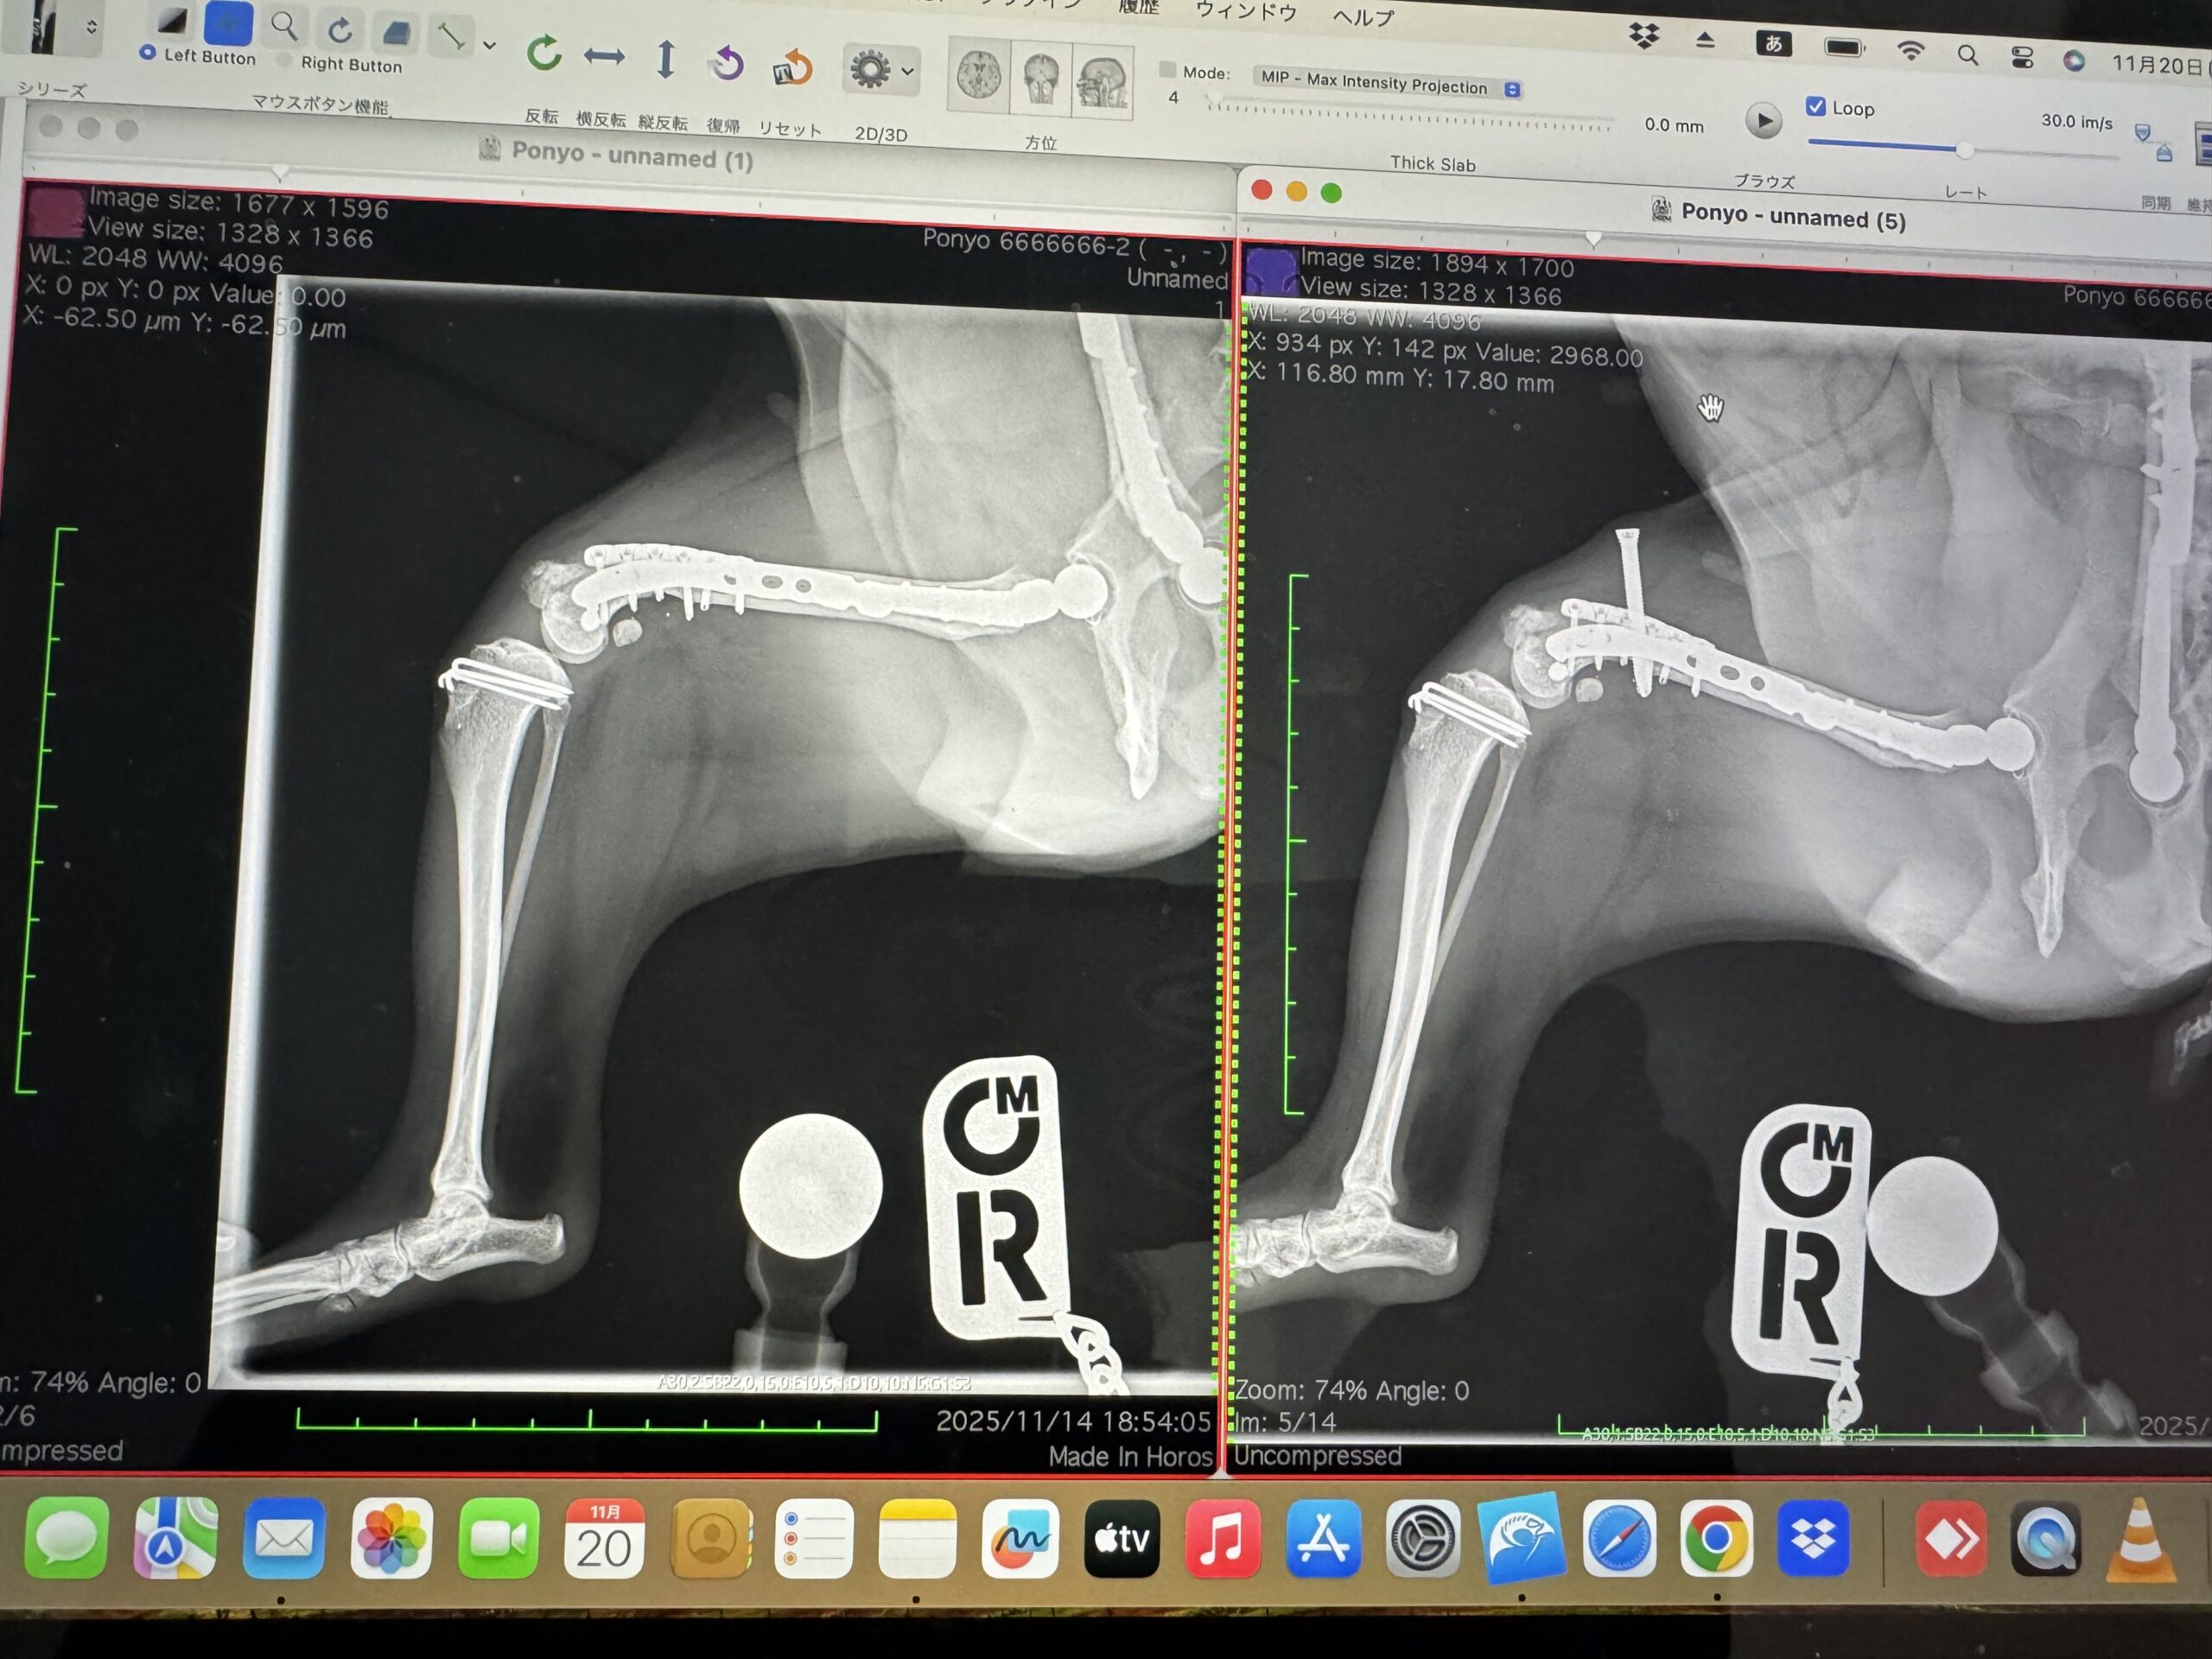

順調に投薬はできていましたが、次の受診で先生の予想通り、手術で入れた人工物に反応が出てきはじめてしまいました。

免疫疾患からみると、人工物は抜ける限りすぐに抜きたい。そうでないと炎症から関節液が溜まって膝のお皿が浮いてしまい再脱臼してしまう。

整形外科的にみると、今抜いたら固着していないのでせっかく手術した足が再脱臼してしまう。

にっちもさっちもいかない、とはまさにこのこと、という綱渡りの状況です。

そのうち後ろの左足の傷からも浸出液が出始め、足をつくこともできないほど痛みも出てきてしまいました。

少し薬を多くして、何とかあと1か月頑張って、抜ける限りのものを抜きましょう、という方針になり、ようやく迎えた手術の日。

11月11日に日帰りの予定で受診をしましたが、薬の量を多くすることで、浸出液も止まり、状況が改善しているはずだった後ろ足の状況がほぼ変わっておらず、その場で術式変更となりました。

予定より多くの人工物を抜く方針になり、手術日が変更となりそのまま入院となりました。

(左が術後、右が術前)